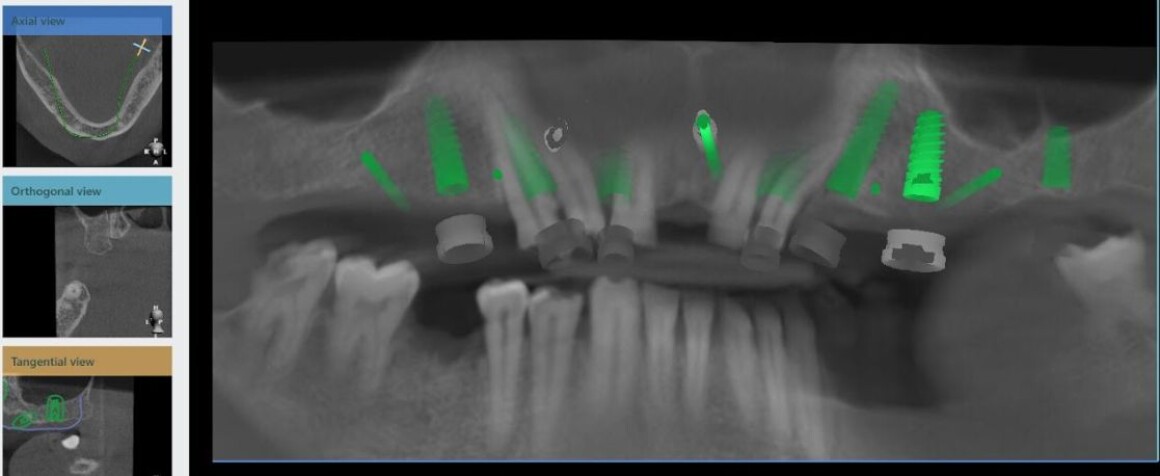

• Планирование имплантации

• Изготовление шаблонов для операции

• Имплантация 12 имплантантов за один раз